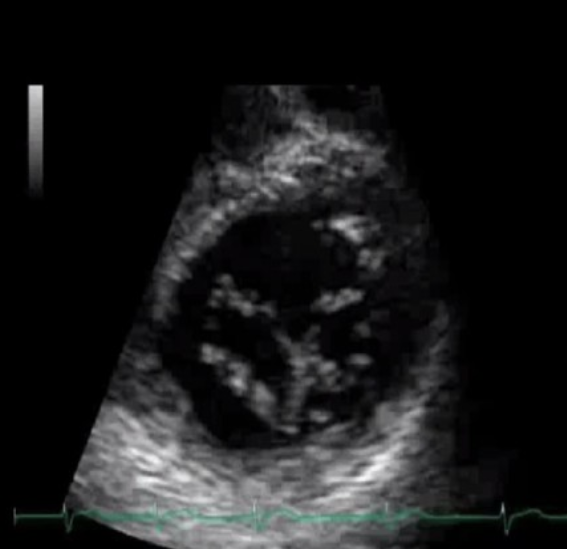

Irregular contour

Abnormal motion

Large trabeculations

Non-compaction cardiomyopathy